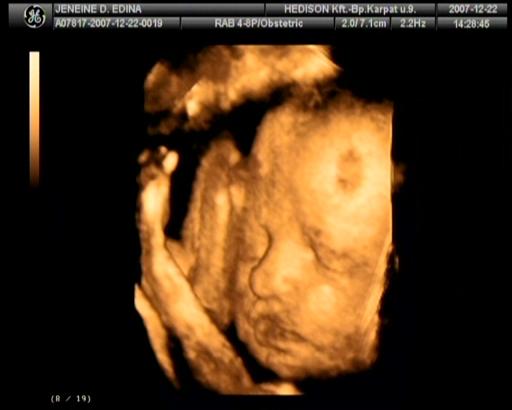

2007.december 25.-re voltunk kiírva. Védőnőm 12. 07.-én pénteken jött hozzánk azzal a céllal, hogy összeírjuk mindazt ami szükséges a nagy napra. Szombaton megvettük a nadrágpelenkát és a popsitörlőt, így már mindent beszereztünk babánknak. Vasárnap még hab mesefigurákat festettünk férjemmel. Nem gondoltuk, hogy valami elkezdődik pocakomban. Este hamar kidöltem,

„szépségápolási” műveletet elvégeztük és elmentem aludni kb. 21:30 -kor. Férjem éjfél körül jött aludni. 12.10.-én 0:30 -kor arra ébredtem, hogy erős vizelési inger kapott el, alig éretm a mosdóba. A nyákdugó távozott magzatvízzel! Halkan szóltam Attinak, hogy kell mennünk. A gyér éjjeli forgalomnak köszönhetően kb.15 perc alatt értünk a Szülészeti Klinikára. Meglepő módon üres volt a parkoló.

Felsétáltunk a szülőszobára és az éjszakás szülésznő felvett az osztályra.

Egy ujjnyira voltam kinyílva. Sétáltam a folyosón, apával csináltunk utolsó pocakos képet Lara a pocakban címszóval, megszakításokkal CTG-n figyeltük Larát és a fájások jelentkezését12:15-ig. Közben reggel Felhívtam fodrászomat, hogy lemondjam a mai időpontot (fodrászom jó szülést kívánt), aztán orvosomat (aki szabadságon volt) 08:00-körül és mondtam, hogy mi a helyzet. Ő bátorított és mondta számíthatok rá, itt van. Délután bejön, addig is délig ihatok folyadékot, aztán bekötik az infúziót. Anyukámat is hívtam, hogy mi lesz a mai programom. Mondta, hogy legyek bátor, picit fájni fog, DE megéri és csak a jóra fogok emlékezni. Mondtam neki, hogy nyugodt vagyok az orvosom is bejön hozzánk a szabadságról.